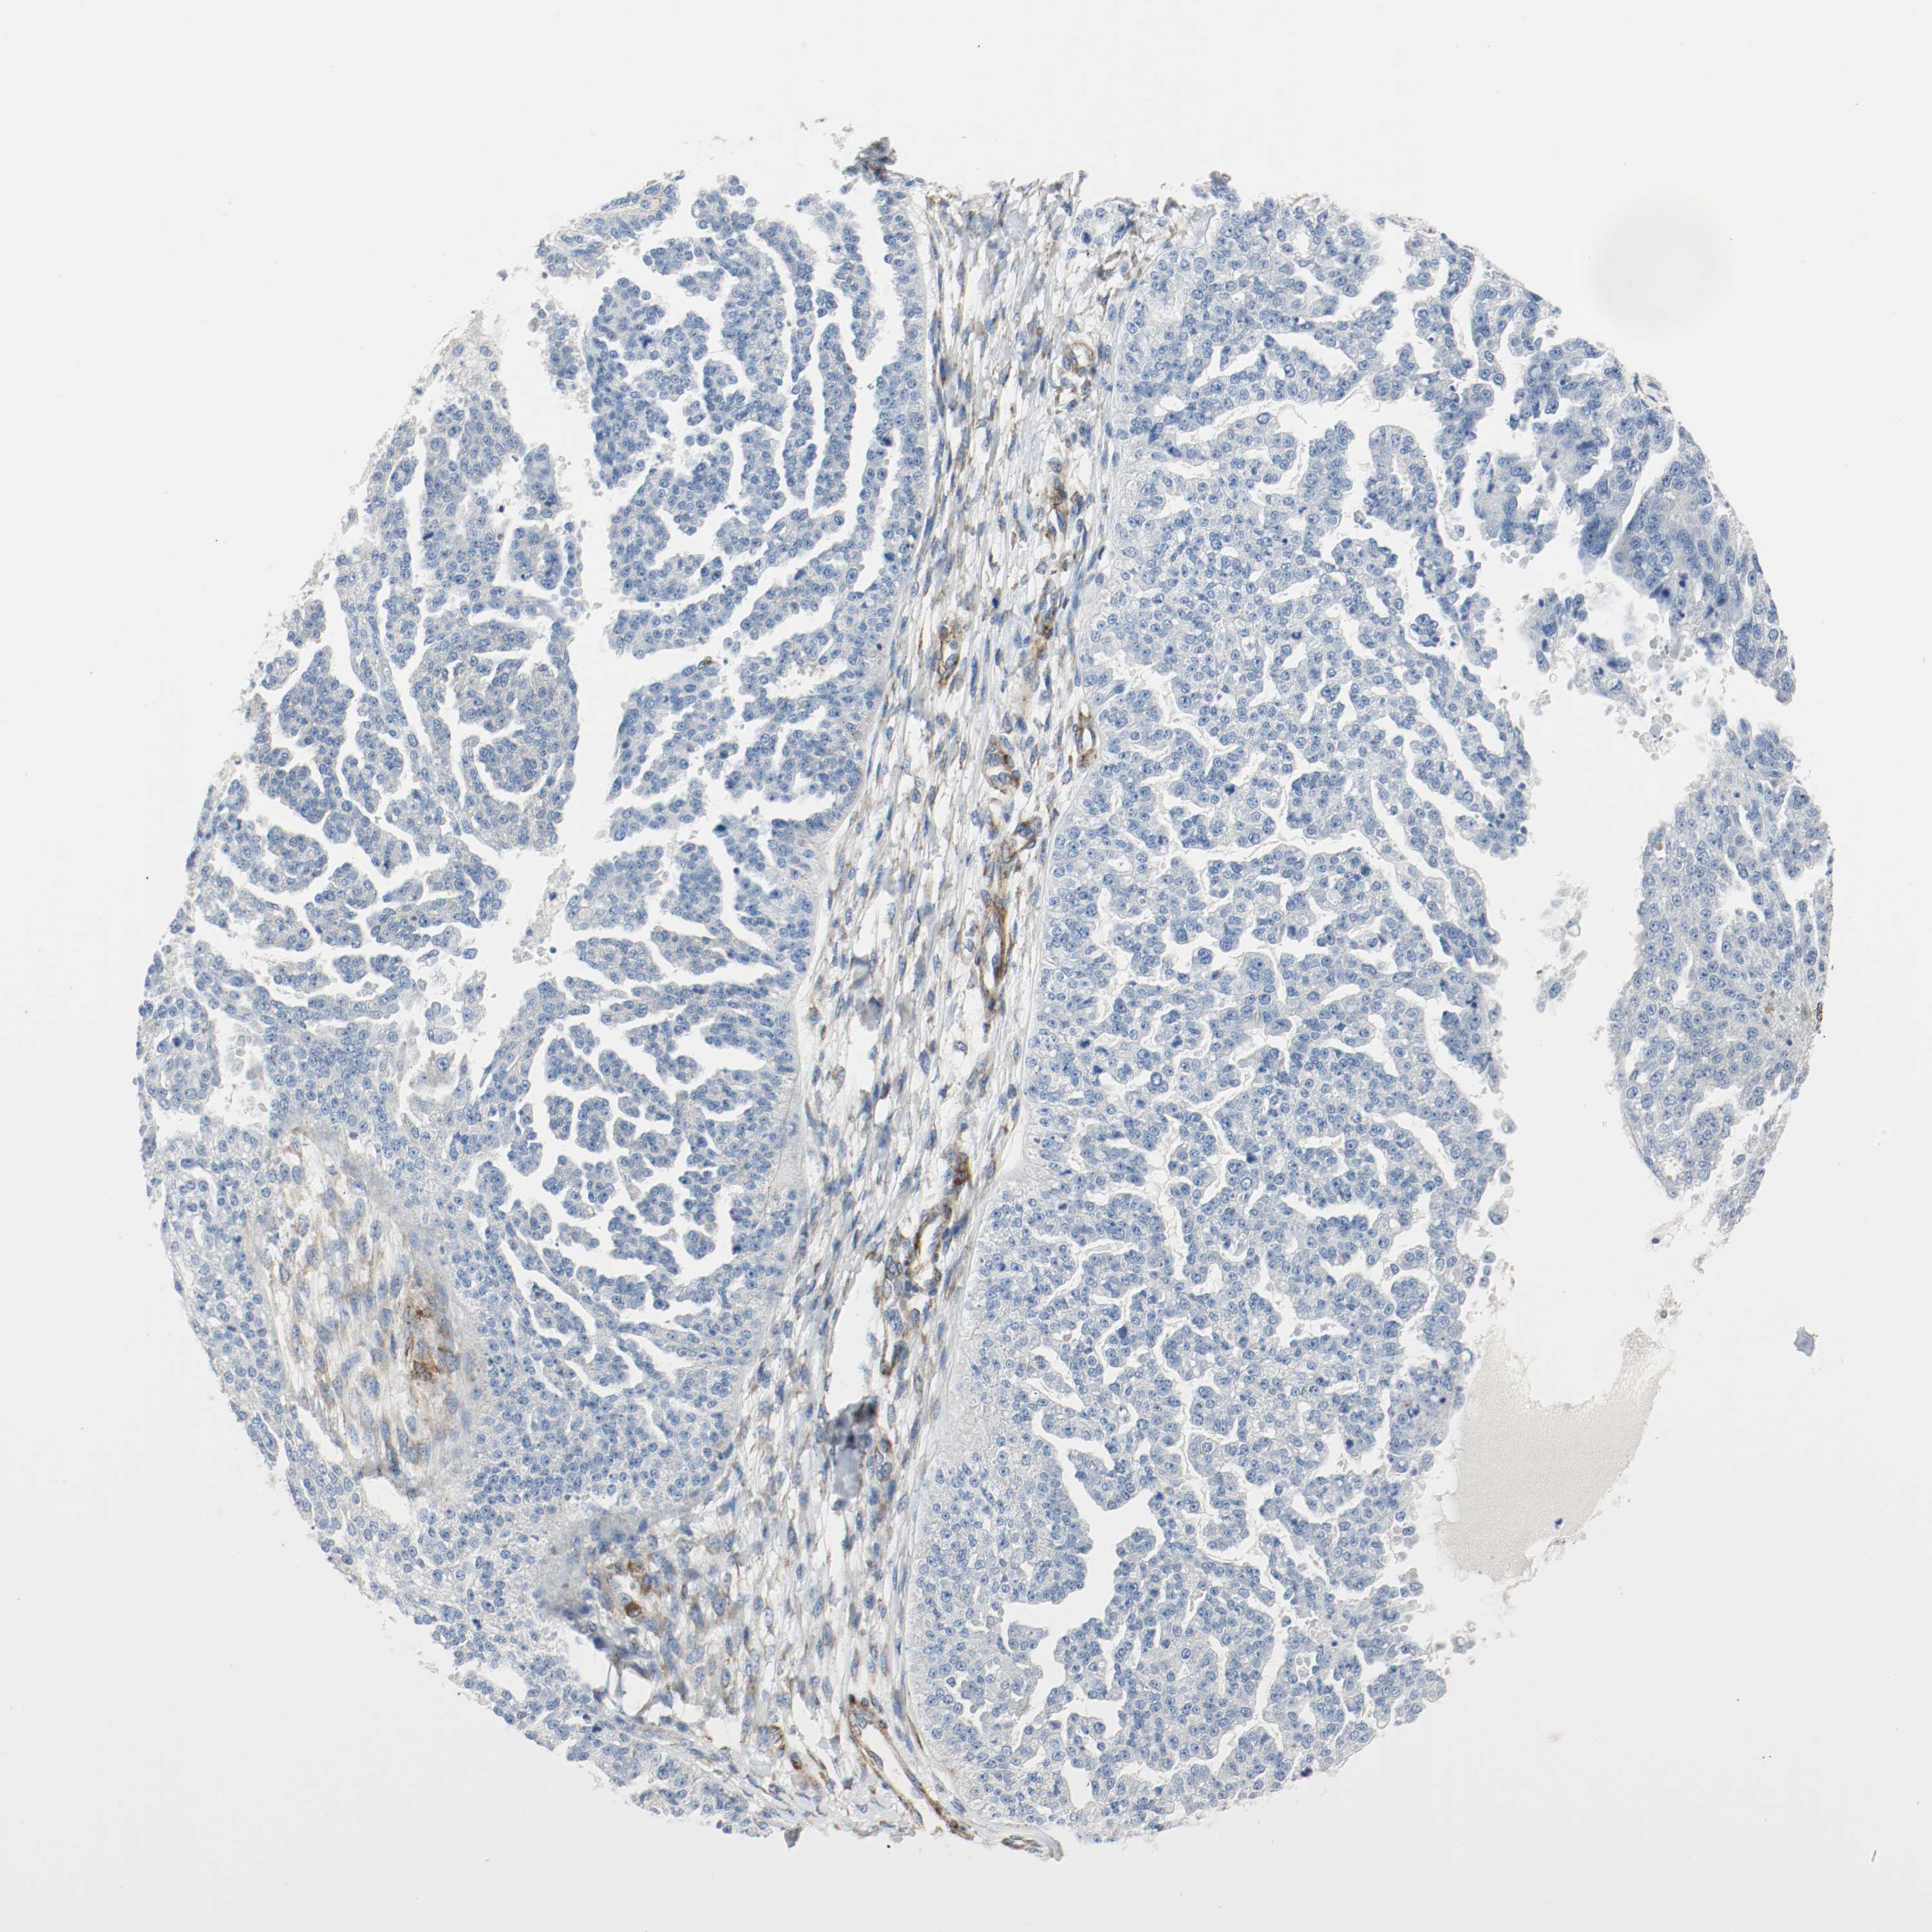

OVARIAN CANCER - Protein expressioni

A mouse-over function shows sample information and annotation data. Click on an image to view it in a full screen mode. Samples can be filtered based on level of antibody staining by selecting one or several of the following categories: high, medium, low and not detected. The assay and annotation is described here.

Note that samples used for immunohistochemistry by the Human Protein Atlas do not correspond to samples in the TCGA dataset.

Antibody stainingi

Antibody staining in the annotated cell types in the current human tissue is reported as not detected, low, medium, or high, based on conventional immunohistochemistry profiling in selected tissues. This score is based on the combination of the staining intensity and fraction of stained cells.

Each image is clickable and will lead to virtual microscopy that enables deeper exploration of all samples and also displays staining intensity scores, fraction scores and subcellular localization as well as patient and tissue information for each sample.

Antibody HPA004056

Antibody HPA004132

Antibody CAB004256

Cystadenocarcinoma, serous, NOS

Carcinoma, endometroid

Carcinoma, NOS

Cystadenocarcinoma, mucinous, NOS